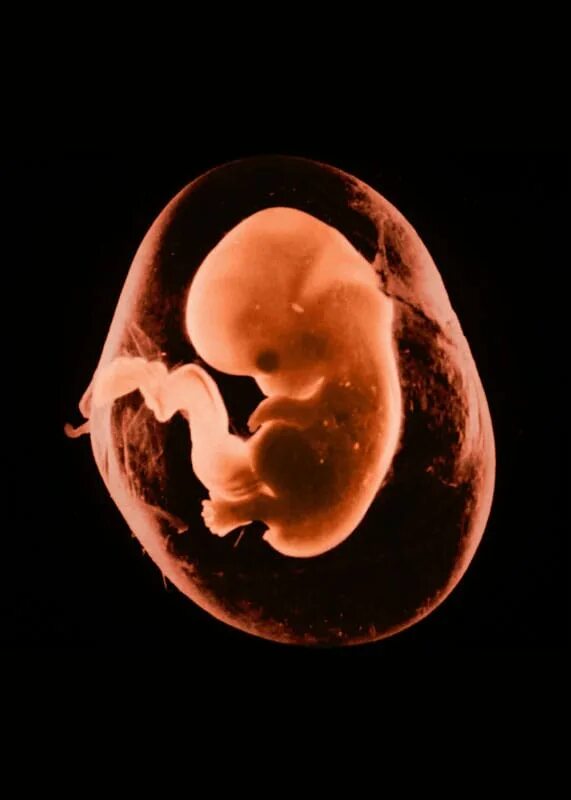

10 week old